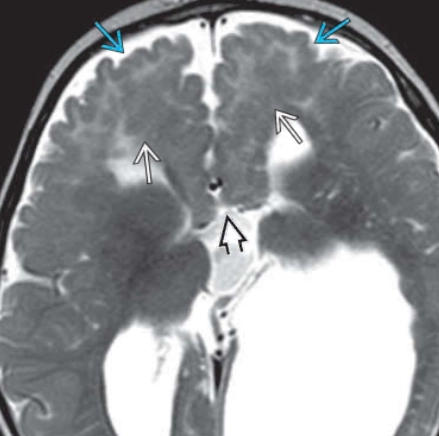

• Chất xám lạc chỗ (Grey Matter Heterotopia)

• Đầu nhỏ (Microcephaly)